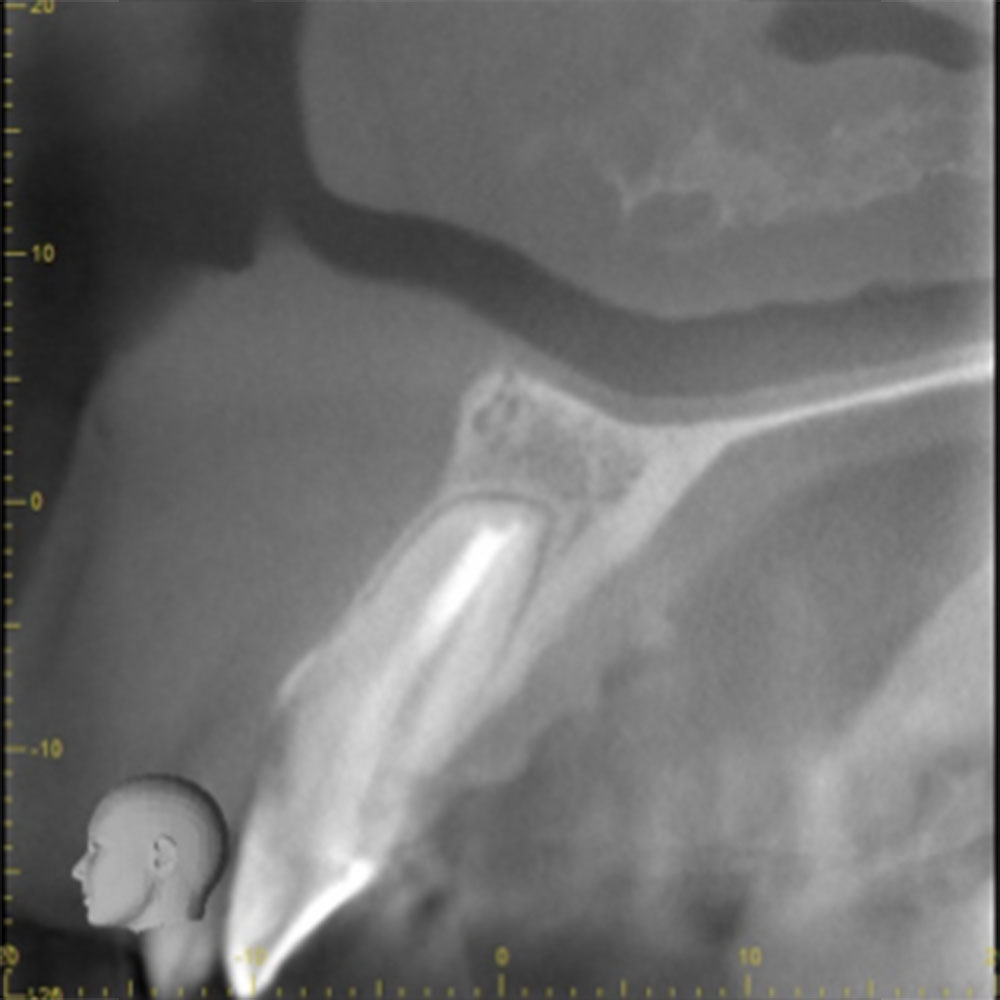

![]() |

| 根の先の黒い影は消失しました。 | 術後6ヶ月のCT画像です。こちらでも、根の先に黒い影は見当たらないです。 |

このように外科的治療で病変部を切除することでしっかりと治癒させることが可能です。根の治療は細菌との戦いです。難しいですが、やりがいがあります。